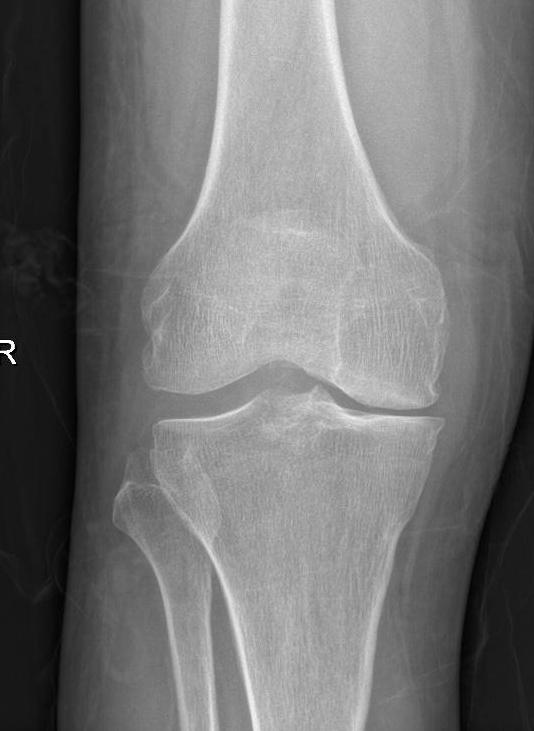

图1 膝骨关节炎x片表现:c晚期

膝骨关节炎的早期表现为膝关节疼痛,随着病情进展,会出现疼痛加重并活动受限,关节畸形。患了膝骨关节炎该如何治疗?首先需明确, 治疗的目的主要是2个,即解决疼痛,改善关节功能。 解决了这两个问题,最终就会实现生活质量的提高。那么如何缓解疼痛?怎样改善功能?这是每个膝骨关节炎患者最关心的问题,这需要根据病情的严重程度,采取个体化的治疗手段。患者希望以最小的代价获得最满意的疗效,这也是医生不竭的医术追求。

重建治疗亦即关节置换治疗,这一阶段所采取的手术方式相对来说是较大的手术了,退变磨损的关节面难以通过自身的修复或局部处理使病情逆转,只能接受表面置换。膝关节表面置换包括部分表面置换术(单髁置换)和全膝关节表面置换术(全膝置换)。通俗来讲,单髁置换主要是解决膝关节内侧或外侧磨损(疼痛)问题,而全膝关节置换是解决全膝关节磨损(疼痛)问题。 重建治疗的手术,是针对骨关节炎的晚期阶段,是终极治疗方式。当然,如果不得不选择这一治疗方式,也大可不必害怕,人工关节置换已经是非常成熟的手术,关节置换术可以有效缓解疼痛、改善功能,使你的膝关节焕发新生,重启人生精彩。

图7 膝骨关节炎全膝关节表面置换术a术前

图7 :a图示双膝骨关节炎严重、外翻畸形。b图示右侧全膝关节表面置换术后